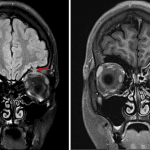

- Ill-defined enhancing osseous lesion in the left orbital roof lateral to the left frontal sinus with intraorbital extension along the superior and lateral margins of the superior muscular complex and slight intracranial extension along the floor of the left anterior cranial fossa with surrounding thin dural thickening and enhancement

- Anterior extension in the lateral extraconal left orbit to the posterior margin of the lacrimal gland

- Moderate mucosal thickening of left anterior ethmoid air cells and the left frontal sinus

- Langerhans cell histiocytosis (LCH)

Enhancing osseous lesion centered in the left orbital roof lateral to the left frontal sinus with intraorbital extension along the superior and lateral margins of the superior muscular complex and slight intracranial extension along the floor of the left anterior cranial fossa. Differential considerations include inflammatory lesions such as IgG4-related disease and Langerhans cell histiocytosis, infection, and neoplasm. Left frontoethmoid sinus disease, which may be reactive and is considered less likely to be the source for the left orbital roof lesion. Consider tissue sampling for further evaluation.